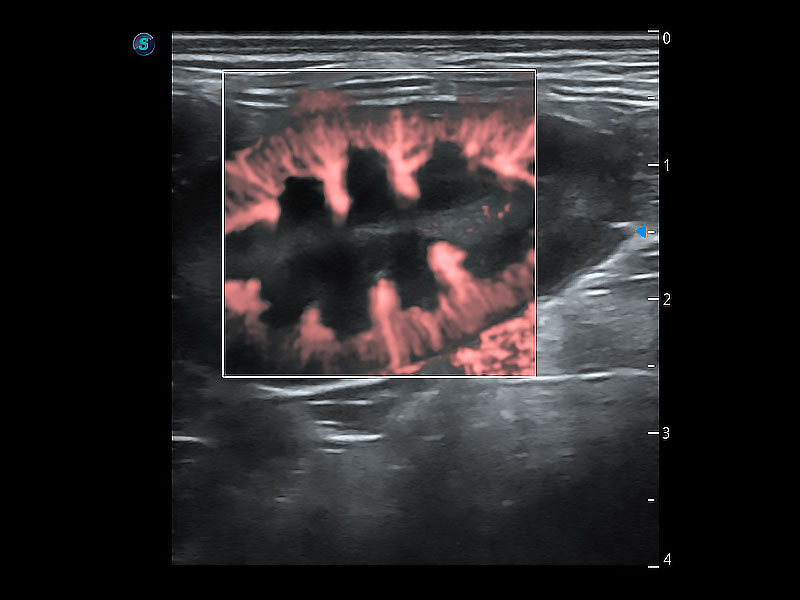

• Bright Flow 立体血流成像

在传统二维血流成像的基础上,呈现血流的立体感,具有动感的生命力之美。即便是微小的血管也能轻松应对,提高了血流的视觉敏感性。

(犬)胎儿主动脉弓立体血流